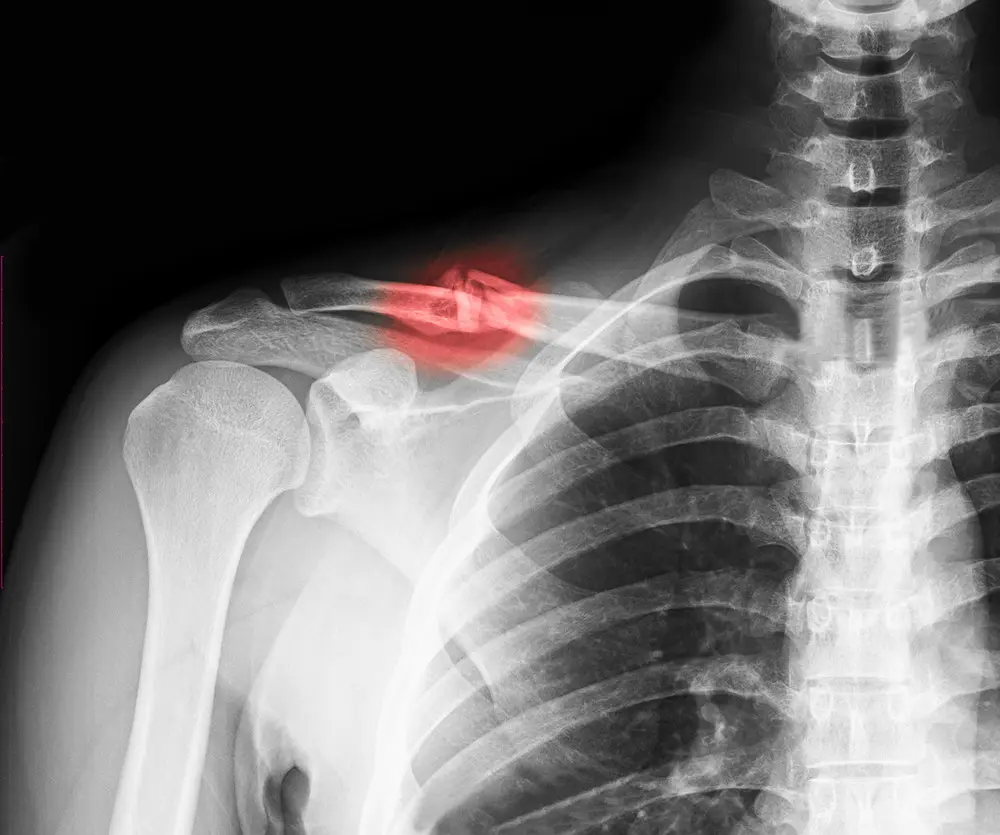

At Bluegrass Orthopaedics, we understand that a fracture of the greater tuberosity affects both the bone and the rotator cuff tendons that control shoulder strength and motion. Our team provides comprehensive, personalized care focused on restoring comfort, function, and long-term shoulder health.

Our board-certified orthopedic specialists have extensive experience treating shoulder fractures, including those associated with rotator cuff injuries or shoulder dislocations. We use advanced imaging and precise evaluations to determine whether non-surgical care or surgical intervention is the best option for your specific injury.